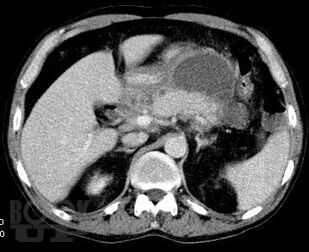

Острый панкреатит. Современные принципы диагностики и лечения

Учебно-методическое пособие посвящено актуальным проблемам этиологии, патогенеза, диагностики, современным методам консервативного и оперативного лечения острого панкреатита Представлены новые классификации, схемы консервативного лечения, современные виды оперативного лечения. Иллюстрировано рисунками, таблицами, имеются тестовые задания и задачи. Пособие предназначено для ординаторов и слушателей дополнительного профессионального образования, обучающихся по специальности 31.08.67 Хирургия.